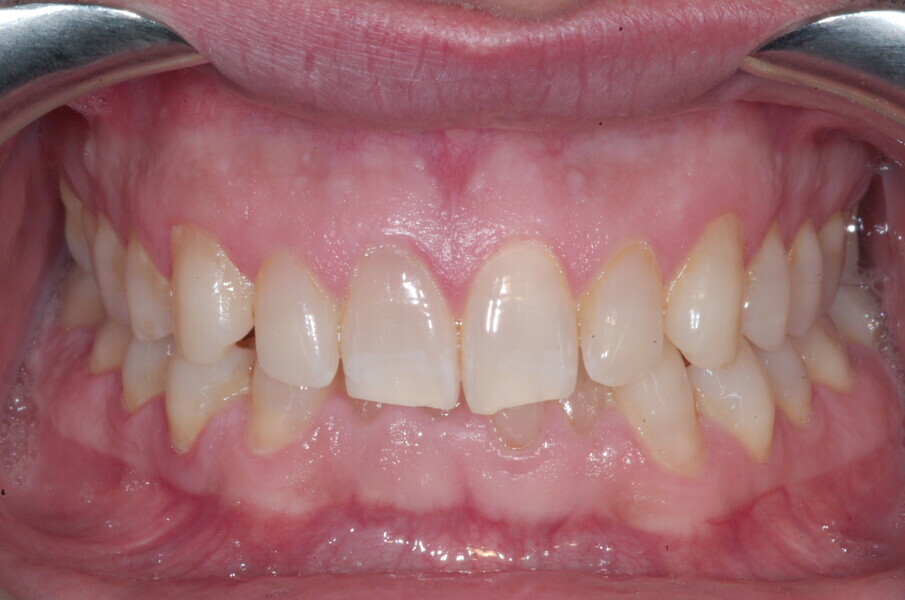

Le motif principal de consultation de ce patient âgé de 37 ans, était de rétablir l’alignement des dents antérieures sur les deux arcades. L’analyse faciale a indiqué une face courte avec un profil plat, mais une projection normale du menton (Figs. 9–12), et l’examen clinique a révélé une classe squelettique de type I (angle ANB = 0,89°) et une malocclusion de classe I avec supraclusion sévère (près de 100 %), une courbe de Spee très prononcée, un torque normal de l’incisive centrale supérieure (Ui-FH = 110°), un encombrement dentaire léger sur l’arcade maxillaire et modéré sur l’arcade mandibulaire (Figs. 13–18). Chez ce patient, les composantes de la supraclusion correspondaient à une dysmorphie squelettique grave correspondant à une hypodivergence (FMA = 14,24°), avec une inclinaison normale des incisives supérieures et inférieures et un angle goniaque réduit (110,46°). L’analyse du cliché céphalométrique indiquait une hauteur réduite de l’étage inférieur de la face associée à l’hypodivergence (Fig. 19). La seule option de traitement envisagée était un traitement orthodontique par aligneurs avec tous les éléments auxiliaires décrits (rampes d’occlusion, zones de pression, nivellement de la courbe de Spee dans les trois dimensions, élastiques de classe II et puissants contacts occlusaux) afin de corriger la supraclusion.

Le plan de traitement numérique (ClinCheck) avait prévu douze aligneurs pour l’arcade maxillaire et dix-sept pour l’arcade mandibulaire. Les objectifs du traitement visaient à combiner les mouvements verticaux d’extrusion des dents postérieures et les mouvements d’intrusion des dents antérieurs, au moyen de rampes d’occlusion, tout en utilisant des taquets d’extrusion pour assurer la désocclusion des dents postérieures et l’intrusion des dents antérieures inférieures, nécessaires au nivellement de l’arcade mandibulaire. La courbe de Spee a été nivelée et le profil plat ainsi que la position des lèvres ont été améliorés par une vestibulo-version des incisives supérieures et inférieures. Le plan avait prévu des élastiques de classe II pour faciliter la vestibulo-version des dents inférieures et les puissants contacts occlusaux postérieurs, avec une extrusion relative des dents postérieures. Une morphologie plus large de l’arcade et une intercuspidation idéale ont été obtenues par des mouvements de torque proches de 0° des dents latérales et postérieures supérieures. Aucune conception technique excessive n’avait été prévue dans le plan de traitement numérique. En raison de l’âge du patient, les aligneurs ont été changés tous les dix jours, dans le cadre d’un traitement d’une durée inférieure à six mois. À la fin de la première série d’aligneurs (Figs. 20–24), un nouveau plan de traitement numérique comportant cinq autres aligneurs a été conçu, en vue d’améliorer l’intercuspidation des molaires sans élastiques. La durée totale du traitement a donc été prolongée jusqu’à 7,5 mois puisque les aligneurs supplémentaires étaient changés toutes les semaines.

À la fin du traitement, on pouvait observer une relation de classe I des canines et des molaires, une légère augmentation de l’inclinaison des incisives supérieures (Ui-FH = 112°), une correction complète de l’inclinaison des incisives inférieures (IMPA = 97,09°) grâce à la vestibulo-version, et une légère amélioration de l’hypodivergence (SN-GoGn = 27°) résultant de l’extrusion relative des dents postérieures, et de l’utilisation d’élastiques de classe II — petite variation (1°) très intéressante compte tenu de l’âge du patient (Figs. 25–35). La ligne du sourire était harmonieuse et correspondait à une relation idéale entre les incisives supérieures et la lèvre inférieure. Le sourire avait été élargi grâce au contrôle du torque des segments latéraux et postérieurs.